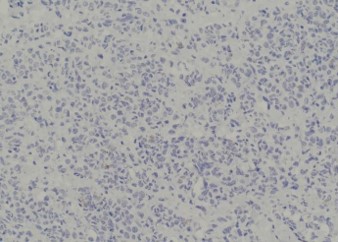

Pathology of the right hemicolectomy specimen was “involvement by metastatic carcinoma, immunoprofile compatible with breast primary”. The cytokeratin profile was CK7+, GATA3+ and MOC-31+, and negative for CK20 and CDX-2. There was very focal positivity for E-cadherin, while p120 catenin mostly showed cytoplasmic staining in the tumour cells. Microscopic examination suggested that the tumour invaded from mucosal side of the intestinal towards the serosa; the proximal and distal resection margins were clear. The morphology and immunoprofile point towards a metastatic carcinoma of breast.